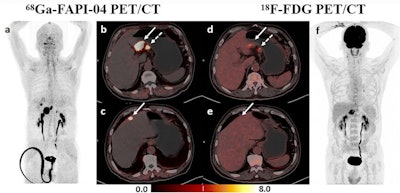

A 44-year-old woman was histopathologically diagnosed with poorly cohesive carcinoma (with partial signet ring cell carcinoma) in the greater curvature of the gastric body and posterior wall of the gastric fundus and had perigastric lymph node metastases. (a-d) Ga-68 FAPI-04 PET/CT imaging. Maximal intensity projection (MIP) image of Ga-68 FAPI-04 PET (a), clear identification of gastric cancer lesions (solid arrow in b, c, and dotted arrow in b) and perigastric metastatic lymph nodes (dotted arrow in c, d). e-h: F-18 FDG-PET/CT imaging. MIP image of F-18 FDG-PET (h), the gastric lesion in the greater curvature of the gastric body (solid arrow in e, f) displayed diffuse mild uptake, the lesions in the posterior wall of the gastric fundus (dotted arrow in e) and perigastric metastatic lymph nodes (dotted arrow in f, g) showed negative uptake. All images courtesy of Ying Miao, Runhua Feng, Zhenggang Zhu, and Biao Li and European Radiology.Ga-labeled quinoline-based FAP inhibitor (FAPI) allows for imaging of tumor stroma by targeting FAP. In studies, Ga-68 FAPI-04 PET/CT has outperformed F-18 FDG PET/CT, especially in cancers of unknown primary origin, breast cancer, and several digestive system tumors, including gastric cancer. It may be an alternative to F-18 FDG PET/CT in detecting these tumors, but the number of SRCC patients involved in previous studies on gastric cancer was limited, according to the authors.